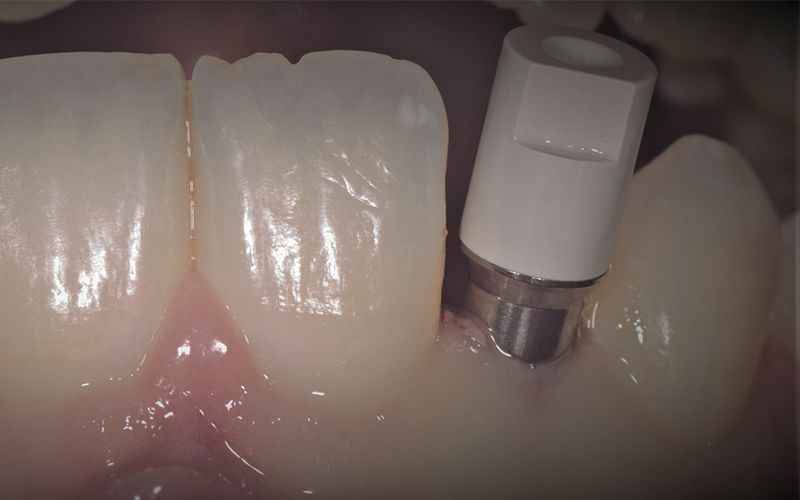

Tras tres meses de osteointegración, se procedió a realizar la segunda cirugía de ambos implantes y se tomaron las impresiones digitales con el escáner intraoral TRIOS (3Shape).

Se mandaron las impresiones a un laboratorio protésicos de confianza para la confección de unos provisionales mientras trabajaban en el diseño y confección CAD-CAM de las coronas definitivas de zirconio.